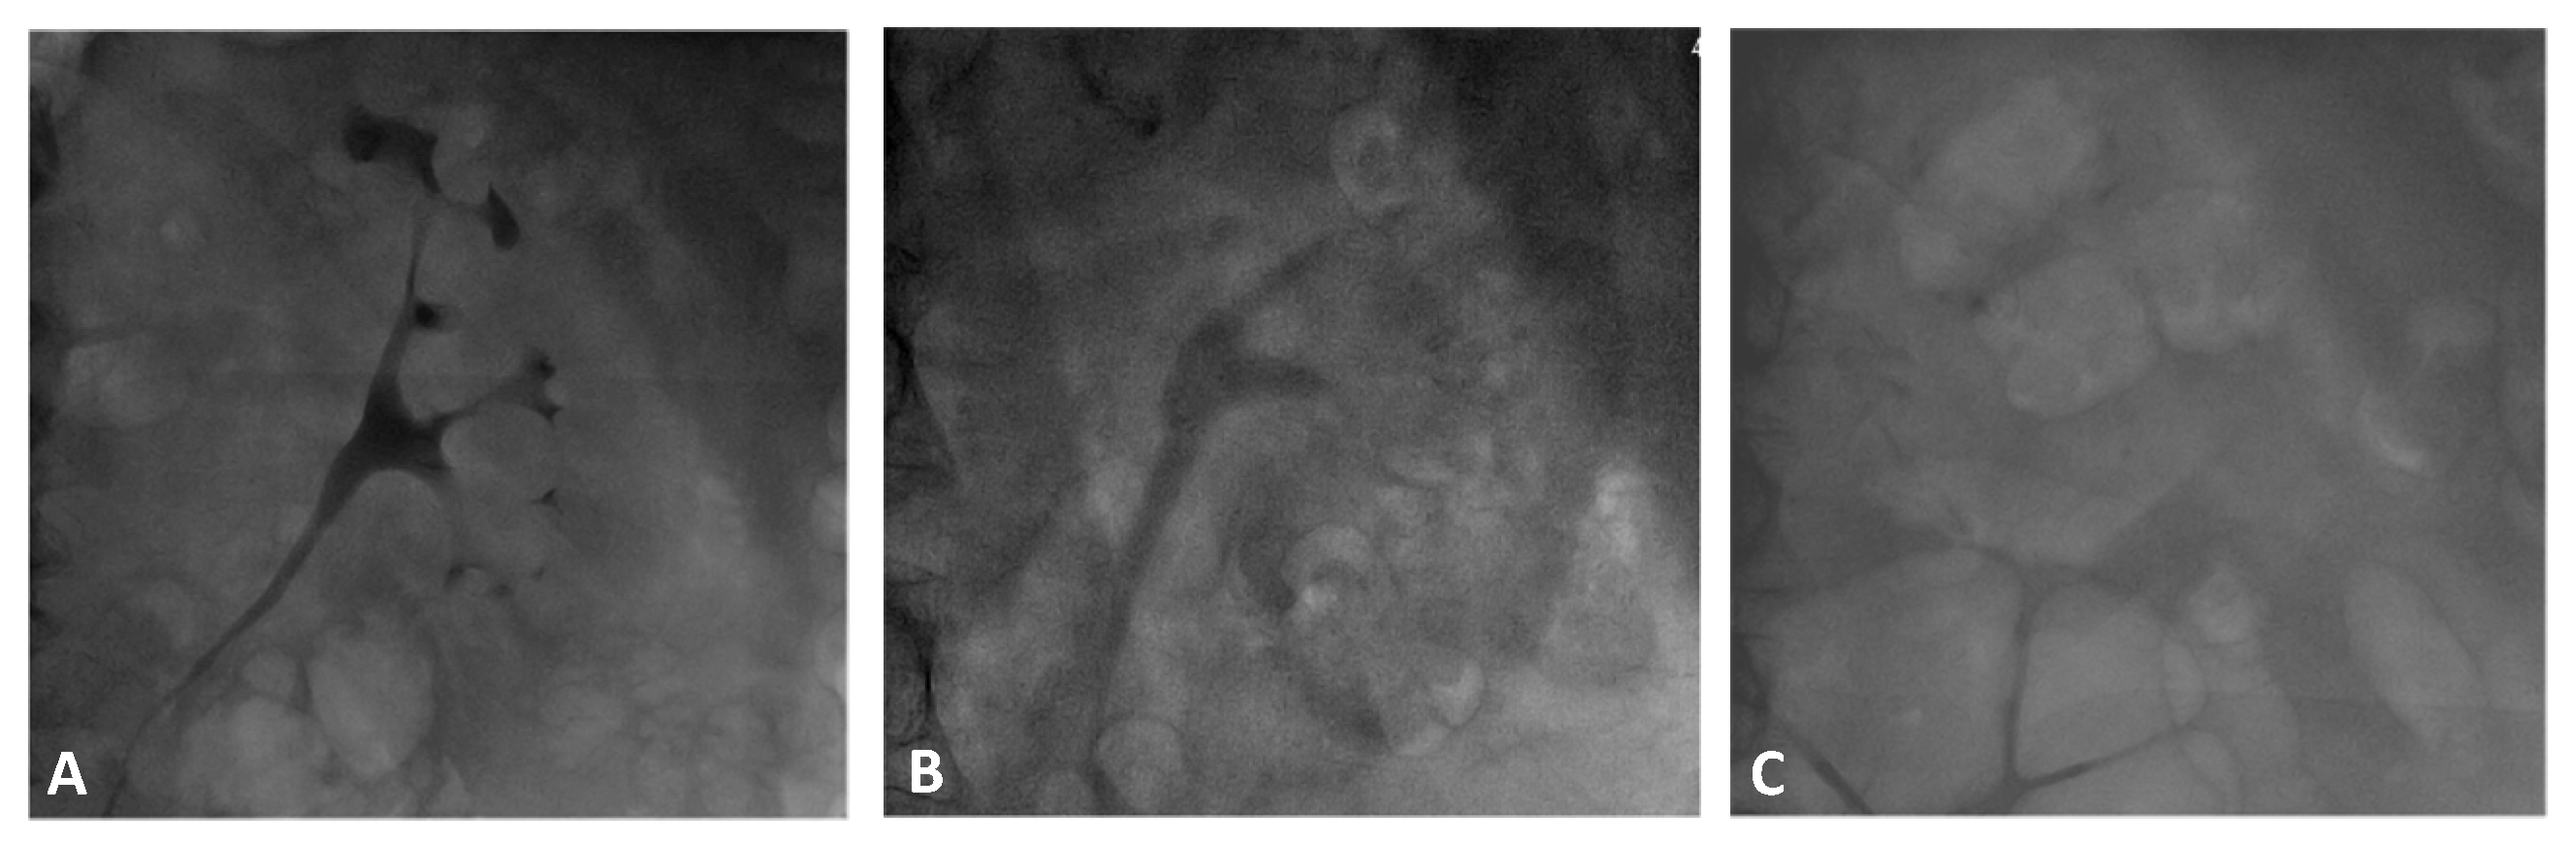

2.3. Renal Contrast Accumulation Analysis